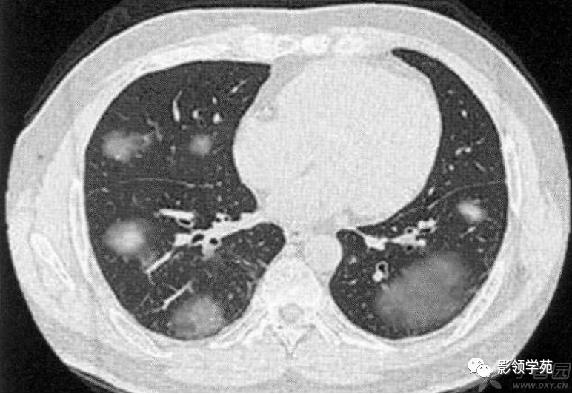

病例3:双肺多发结节伴空洞,部分空洞见气液平面。

肺内多发结节和肿块是肺Wegener肉芽肿最常见的影像征象,表现为两肺散在分布、多发大小不等类圆形结节或肿块影,以两肺中下野分布多见。部分结节和肿块内可见空洞,洞壁多较厚,内缘光滑或不规则,空洞呈边缘性强化。合并感染时空洞内可形成液-气平面。结节或肿块周围一般都有较短毛刺,部分病灶有长毛刺与邻近的胸膜相连,表现为胸膜凹陷征。这与病理上结节周围存在大量成纤维细胞以及以纤维化形式愈合有关。

结节或肿块周围可见晕轮征、供养血管征。晕轮征提示肺结节或肿块出血,CT表现为结节或肿块周围磨玻璃密度影;供养血管征CT表现为血管影进入结节或肿块内,提示病变以血管为中心生长。